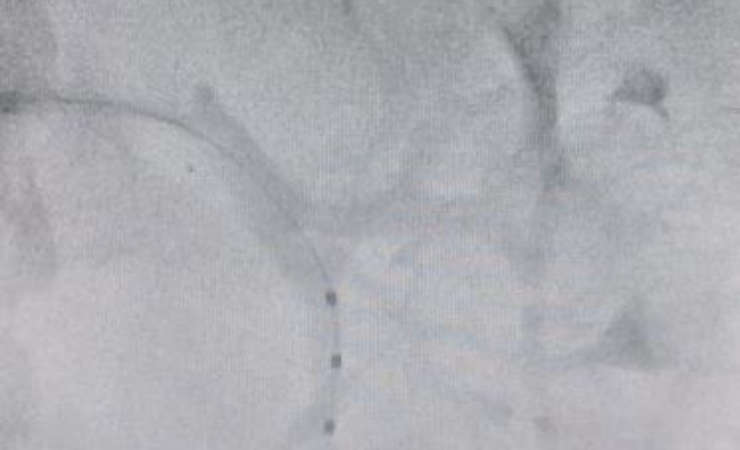

术前,副院长范晓涌,北大人民医院教授王伟民与心内科主任佟勤红及科室相关人员召开病例讨论会,决定对患者进行RDN高血压介入手术治疗。选择股动脉路径进行穿刺,在导丝引导下将Symplicity Spyral消融导管送至消融的部位并分别进行消融,消融双肾主干及分支部位65个点位,对双侧的肾动脉进行了全面、完整的消融。整个手术过程耗时1小时。消融后肾动脉无痉挛、狭窄、夹层等并发症,手术获得圆满成功。鉴于RDN治疗效果最佳观察期为术后3个月,故目前继续服用降压药物治疗,后续将对患者进行密切随访观察,根据血压情况进一步调整治疗方案。